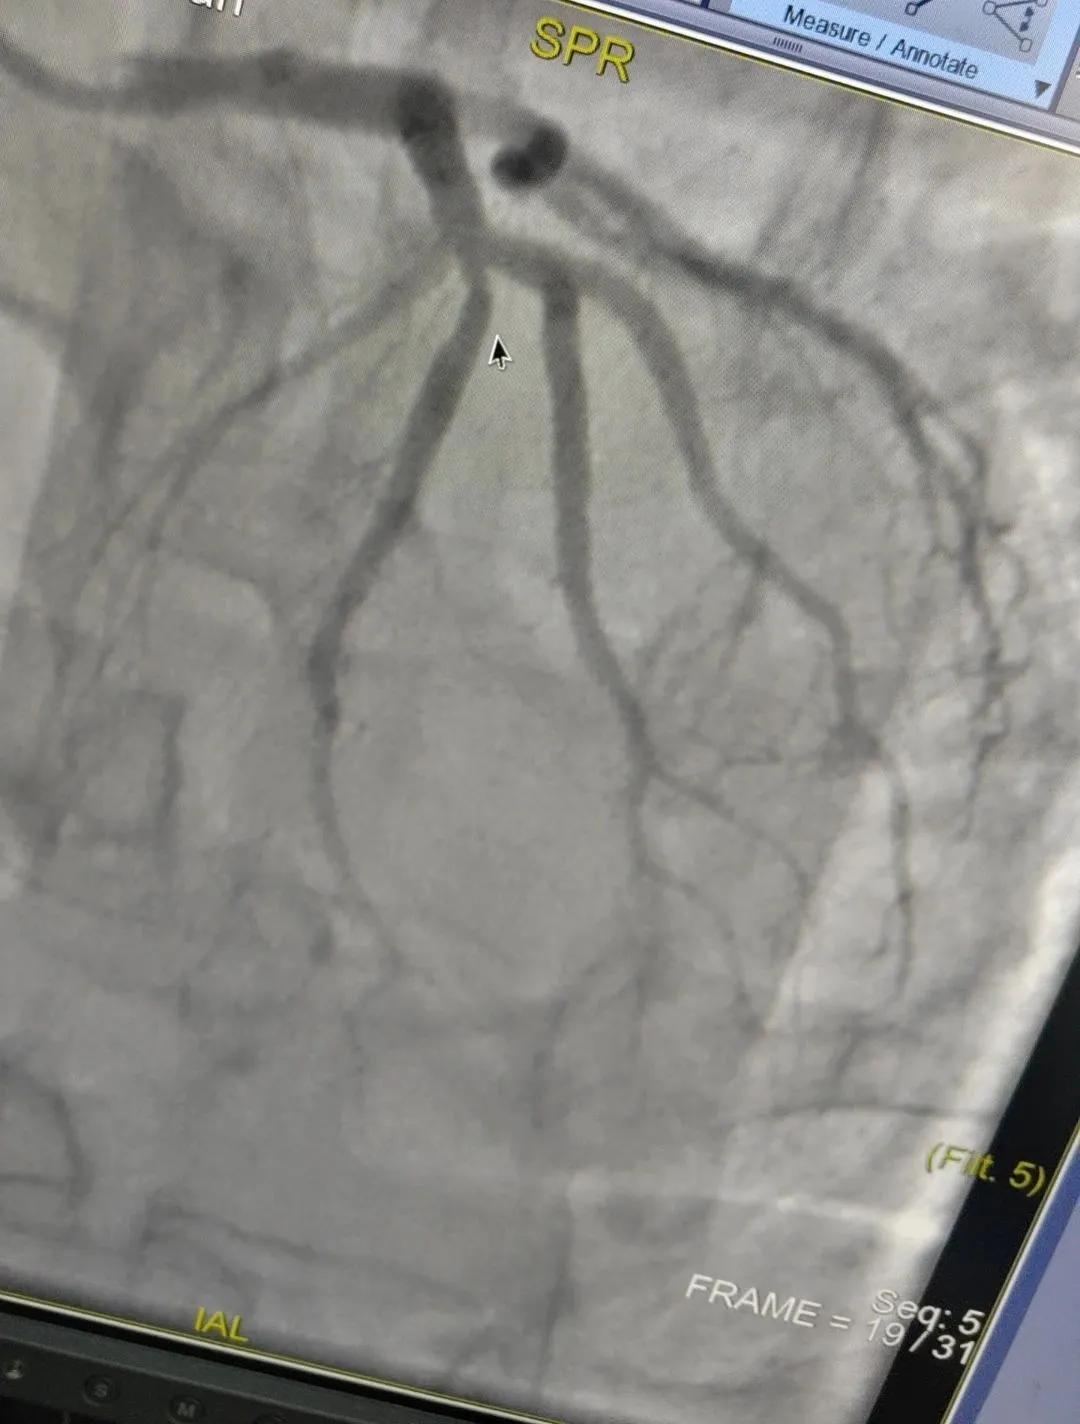

近日,漯河市中醫(yī)院成功開展了一例心腦血管聯(lián)合造影的手術。

患者男,37歲,兩周前無明顯誘因突發(fā)頭昏,伴右側(cè)肢體無力來院就診,經(jīng)過對患者病情的評估以及心內(nèi)科和腦病科醫(yī)生聯(lián)合會診,需對患者進行心腦血管聯(lián)合造影手術。由神經(jīng)內(nèi)科楊慶堂副主任與心血管內(nèi)科陳云副主任帶領各自的介入團隊為該患者順利進行了全腦血管造影術+心血管造影的介入檢查。

術中心血管造影顯示:LAD中段發(fā)出D1處可見約50%節(jié)段性狹窄,RCA中段狹窄約40%,PLA可見約70%狹窄病變。

腦血管造影顯示:左側(cè)頸內(nèi)動脈嚴重遷曲,左側(cè)大腦前動脈未顯影,左側(cè)大腦中動脈M1中段以遠未顯影,M1近段串珠樣嚴重狹窄,顱底可見少量煙霧血管,后交通動脈未開放;右側(cè)頸內(nèi)動脈嚴重遷曲。右側(cè)大腦前動脈A1段嚴重遷曲。

心腦聯(lián)合造影不僅明確患者的病因和病變血管,還為下一步治療提供了有力的依據(jù)。